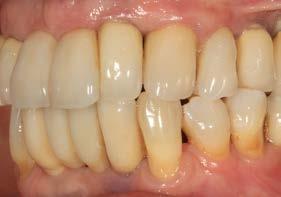

Un año más tarde, al finalizar el periodo de seguimiento (24 años), las fotografías intraorales evidenciaron ligeras alteraciones de los tejidos blandos, con pequeñas troneras abiertas,

más evidentes en los dientes naturales conservados que en las restauraciones implantosoportadas. A pesar de estos cambios, el resultado global se consideró satisfactorio desde el punto de vista funcional y estético, especialmente en comparación con la situación clínica y radiográfica inicial previa al tratamiento (Figuras 26–31).

Figuras 26–29. Imágenes clínicas a los 25 años. Se aprecia mínima pérdida ósea en dientes e implantes, con ligera apertura de troneras. Considerando el antecedente periodontal de la paciente, estos cambios pueden considerarse compatibles con una evolución controlada bajo mantenimiento estricto.

Los hallazgos observados en el caso presentado se alinean con esta evidencia, al documentar la estabilidad durante 25 años tanto de los implantes como de dientes que, en el momento inicial, presentaban un pronóstico claramente comprometido. Esta evolución refuerza la idea de que la pérdida ósea inicial no debe considerarse un criterio absoluto de exodoncia, especialmente cuando existen posibilidades reales de control de la enfermedad y seguimiento continuad.36-39 Asimismo, el hecho de que las alteraciones tisulares finales se manifestaran de forma más evidente en los dientes naturales conservados que en los implantes subraya la naturaleza dinámica del periodonto a largo plazo y la necesidad de reevaluaciones periódicas del pronóstico, incluso bajo condiciones óptimas de mantenimiento.22,23,36

Figuras 30 y 31. Comparativa inicial y final a los 25 años de seguimiento, que muestra la estabilidad alcanzada tanto en los dientes conservados como en los implantes.